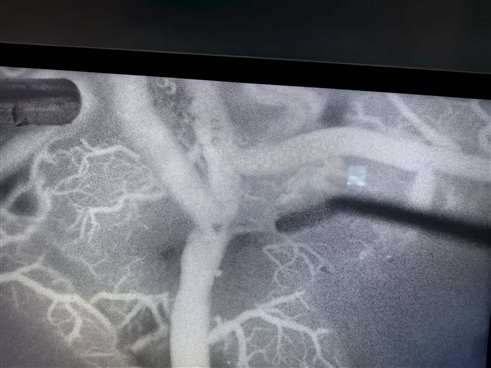

烟雾病,可不是空气中的“烟雾”跑进身体里了。它其实是一种慢性进行性脑血管疾病,主要是大脑底部的大血管末端出现狭窄或闭塞,管腔变细,导致血流不通畅,脑组织缺血缺氧。为了弥补这部分脑组织的供血不足,人体通过自身调节机制会慢慢开通颅底一些非常细小脆弱的“异常血管网”来补偿供血。在脑血管造影检查中,这些密密麻麻的“异常血管网”看起来就像一团烟雾,“烟雾病”因此得名。它可是导致脑出血、脑缺血的“罪魁祸首”之一 ,儿童和成年人均有患病的可能。

1. 脑血管造影(DSA)——金标准

通过股动脉插管注入造影剂,三维重建显示:

颈内动脉"鼠尾征"(渐进性狭窄)

脑底"烟雾云"(异常血管网)

侧支循环代偿情况